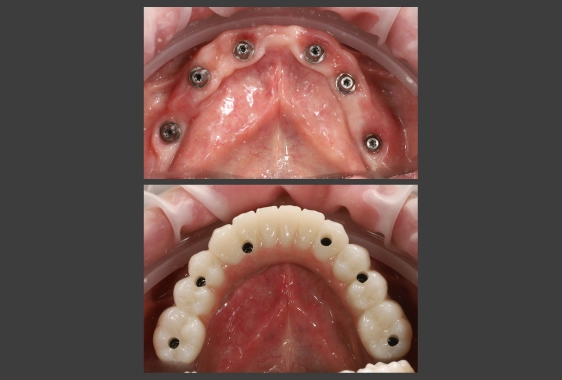

Хірургічний шаблон являє собою персоналізовану 3D-навігаційна капу з отворами для імплантів. Він виготовляється персонально під пацієнта та фіксується в ротовій порожнині протягом імплантації. Трафарет задає точний вектор, глибину, кут нахилу імпланту, забезпечуючи йому довгострокову стабільність і функціональність.

При імплантації без шаблону хірург орієнтується на клінічні маркери, форму альвеолярного гребеня, тактильні відчуття. За давньої втрати зубів анатомія щелепи змінюється, тому візуальні орієнтири стають нечіткими. Навігаційний шаблон мінімізує похибки та підвищує точність операції. Лікар вкручує імпланти в готові отвори, що гарантує точну відповідність попереднім розрахункам.

Імплантація за шаблоном дозволяє уникнути фатальних помилок: перфорації оболонки гайморової пазухи, пошкодження нерва, надмірного нахилу чи зміщення імпланту в процесі укручування. У типових випадках інструмент скорочує час операції.

- точне встановлення імплантів забезпечує надійну фіксацію, отже – стабільність протезів;